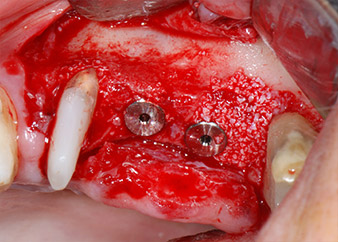

Un mois plus tard, le jour de l'intervention, la douleur et l'inflammation sur la dent 24 étaient minimes mais une mobilité de classe 2 de Miller était toujours observable. Après ouverture des lambeaux et nettoyage des tissus périapicaux et périradiculaires infectés, l'étendue du défaut osseux est devenue parfaitement visible (Figures 2 et 3).

Avant la pose de l'implant, les tissus infectés ont été retirés de l'os alvéolaire sur le site de l'implant et autour des dents piliers à l'aide d'un insert initialement conçu pour le façonnage de l'os et la récupération des copeaux d'os (Piezomed, insert B5) (Figures 6 et 7).

Les lits implantaires ont été préparés sur les sites 25 et 26 à l'aide d'instruments rotatifs, utilisés dans un contre-angle avec un rapport de transmission 20:1 avec un nouveau moteur d'implantologie puissant (Implantmed, W&H) (Fig. 8).

Les implants (Restore, Keystone Dental, 3,75 mm de diamètre, 8,0 mm de long) ont été mis en place à l'aide du moteur d'implantologie (Fig. 11 et 12).